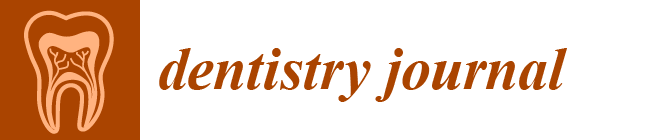

2.1. Defect Model Fabrication

2.2. Sample Fabrication for Comparison Experiments

2.2.1. Conventional Impression Technique